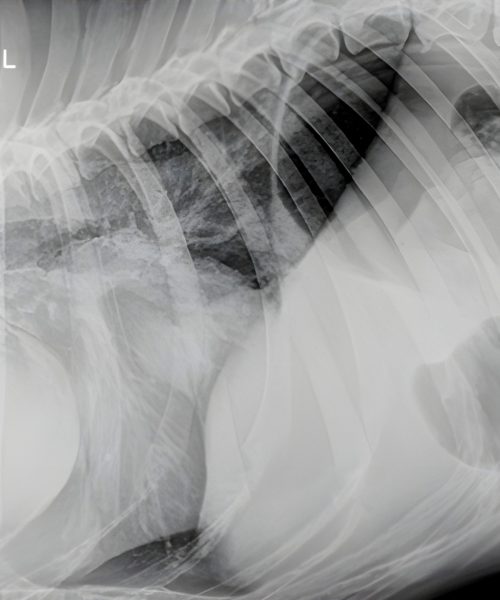

Ofrezco especialización en ecografía veterinaria y una colaboración integral basada en vuestro historial clínico.

Valido la precisión diagnóstica comparando las imágenes ecográficas con los hallazgos quirúrgicos reales.

Garantizo transparencia y confianza exhibiendo en este apartado casos reales con su correlación intraoperatoria documentada.